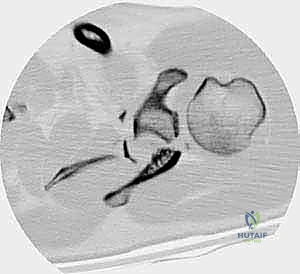

Operative Techniques in Orthopaedic Surgery